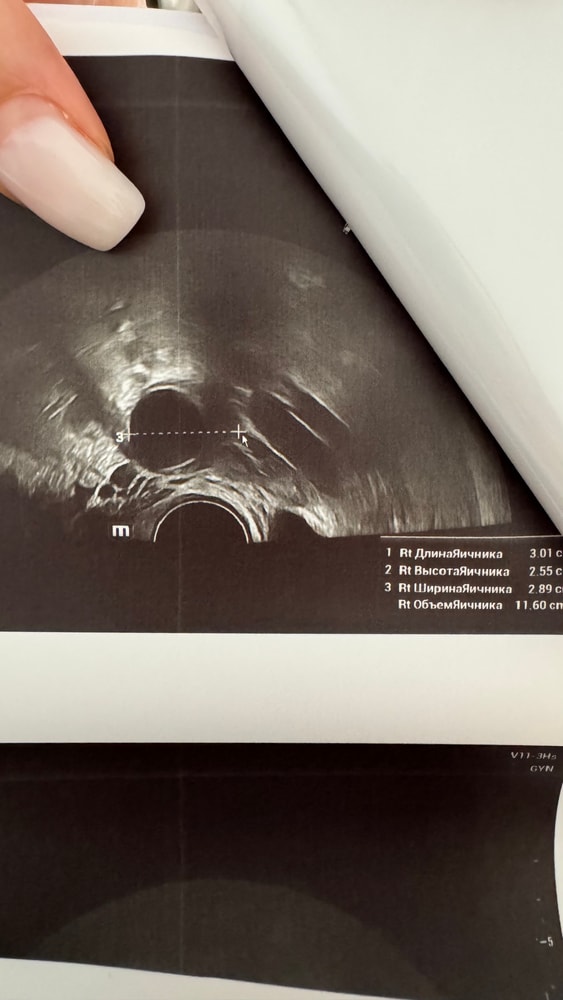

ДФ 24 мм, на 17 дц

узи :дф 24 мм, эндометрий 13мм однородный.

Таня, блин, сложно конечно, может я ошибаюсь, но на фото 👆с линейкой и цифрой 3 это же размер яичника. ДФ черным, и линейка явно не его мерит. Нет? Не понимаю.